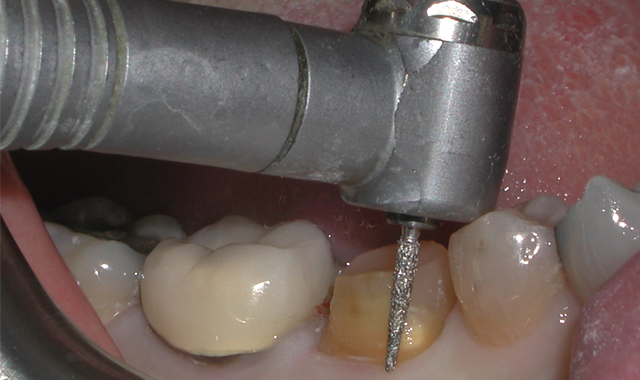

Fig. 4 Fig. 5

The first step in preparation of tooth #30 for a PFM crown is reduction of the clinical crown in the buccal and lingual dimensions. This was accomplished using a flat-ended taper diamond bur (Premier Dental, Solo Diamond #846KR016C) to create rounded internal line angles (Fig. 5).

Next, interproximal contacts are broken using a round end-taper diamond bur (Premier Dental, Solo Diamond #850012C), followed by occlusal reduction and shaping using a football diamond bur (Premier Dental, Solo Diamond #368T023C) (Figs. 6-7). Proper axial reduction for a PFM crown should be 1.0-1.5 mm and occlusal reduction of 1.5-2.0 mm in the central fossa.